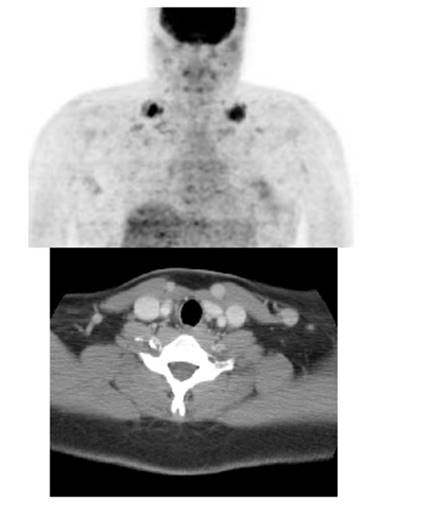

Figure 5 - Genitourinary activity: The image below demonstrates normal

renal and hepatic activity.

Figure 6 - Genitourinary activity: The image below

demonstrates activity within the collecting system of a transplanted kidney

(black arrows). This should not be mistaken for an abnormality.